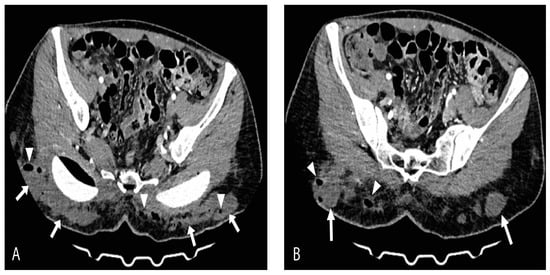

2. Case Report